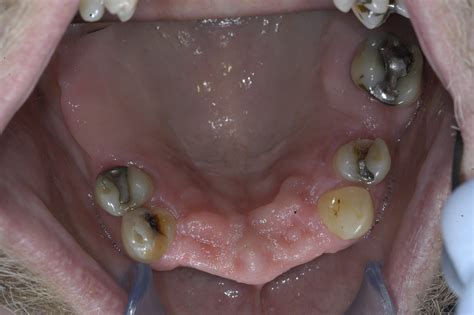

Gingivectomy is a dental procedure that involves the removal of gum tissue to address gum conditions such as periodontitis. This procedure is usually recommended when the pockets between the teeth and gums are too deep and cannot be cleaned with traditional methods.

Gingivectomy is necessary when gum conditions such as periodontitis are not treated in their early stages. If left untreated, these conditions can cause inflammation and damage to the gum tissue, leading to tooth loss. Gingivectomy helps to remove the damaged gum tissue, allowing for the healthy tissue to grow back and prevent further damage.

Gingivitis, or inflamed gums, is a common dental problem that affects millions of people worldwide. While it may seem like a minor issue, left untreated, gingivitis can lead to more serious oral health problems, such as periodontitis and tooth loss. One effective treatment for chronic gingivitis is gingivectomy, a surgical procedure that removes excess gum tissue and allows for better oral hygiene.

Gingivectomy is a relatively straightforward surgical procedure that can be performed under local anesthesia in a dental office. The procedure involves removing excess gum tissue that has grown over teeth due to inflammation. This allows for better access to teeth for cleaning, which can help prevent further gum inflammation. Gingivectomy can also be used to reshape gums to improve their appearance. While it is generally safe, there are potential risks associated with the procedure, including bleeding, infection, and sensitivity.